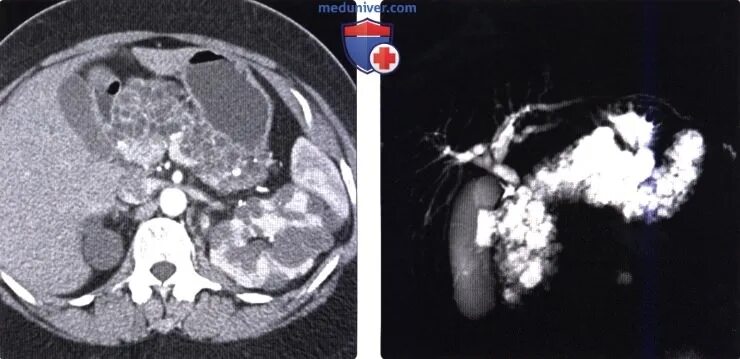

Мрт кисты поджелудочной